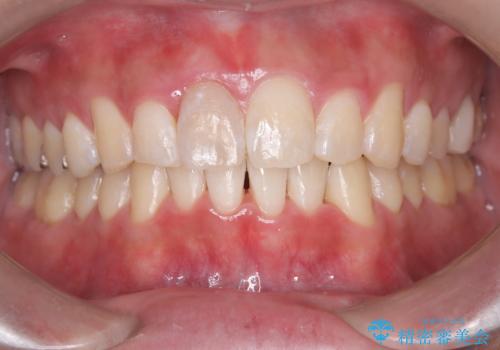

- 「歯のデコボコと前歯が引っ込んでいるのを治したい」を主訴に来院された患者様です。

デコボコの量が多かったため上下左右4を抜歯してワイヤー矯正で治療を行いました。

正面から見たときに右上2が全く見えないくらい、右上2が後ろに引っ込んでいる状態でしたが綺麗に並べる事が出来ました。